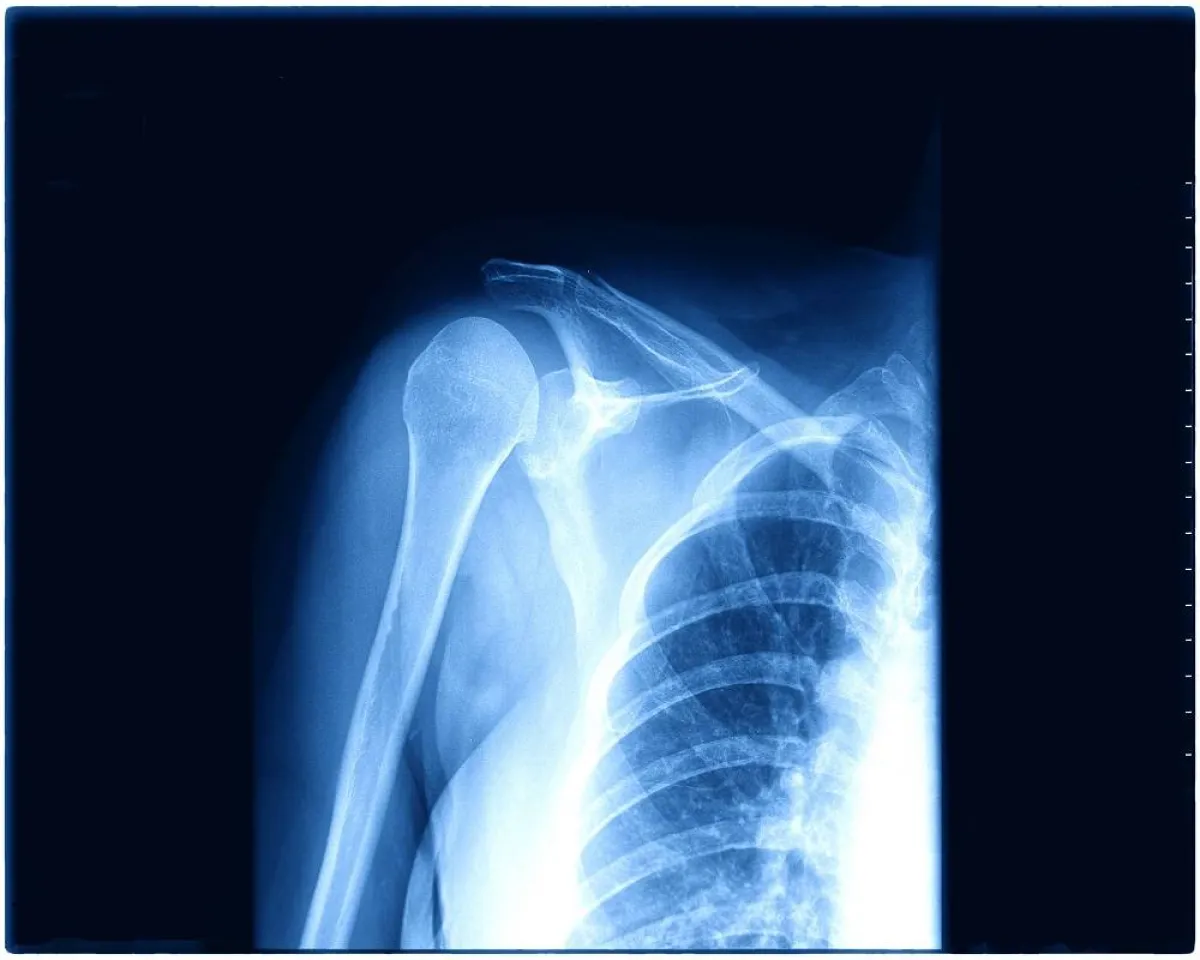

تشخيص كسر الترقوة عند الأطفال

2- فحوصات التصوير

قد يقترح الطبيب إجراء أشعة سينية بعد الفحص البدني في حالة الاشتباه في حدوث كسر. قد يُطلب إجراء فحص بالأشعة المقطعية أيضاً؛ لمراقبة الكسور الشديدة وكسر العظام في بعض الحالات.